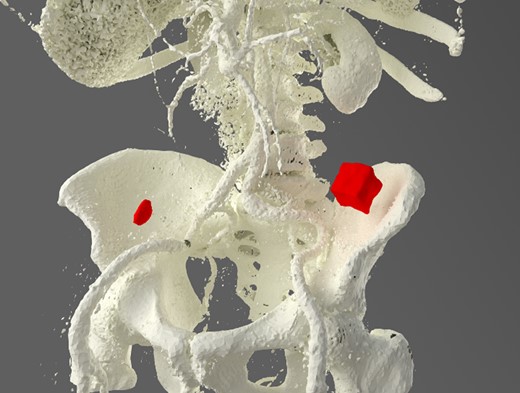

A 92-year male, with no significant co-morbidities apart from peptic ulcers, was admitted with 6 days of obstination. On examination he was dehydrated, with a hugely distended abdomen but no signs of peritonitis. Blood showed features of dehydration and plain abdominal X-ray demonstrated both small and large bowel dilatation, but no obvious causal pathology. A contrast-enhanced computed tomography scan revealed a 2.5-cm partially calcified gallstone impacted at the descending colon-sigmoid junction (Fig. 1). There was no stricture or diverticular disease distal to the stone. A cholecysto-colic fistula could be seen (Fig. 2), with a further smaller gallstone in the caecum (Fig. 3). The offending gallstone could be seen incidentally in the gallbladder on imaging 3 years previously (Fig. 4).

The offending gallstone as an incidental finding 3 years previously.